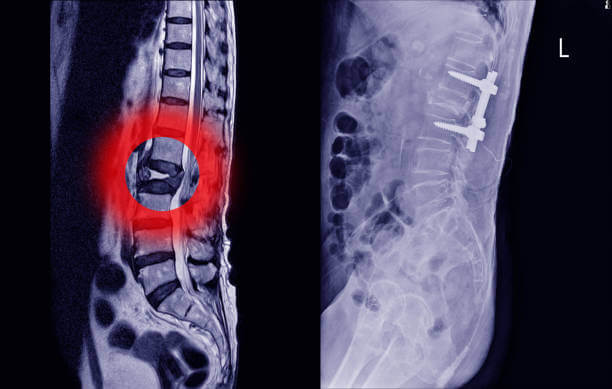

허리디스크(추간판 탈출증)은 척추뼈와 척추뼈 사이의 구조물인 디스크가 탈출된 상태입니다. 일반적으로 허리디스크라고 부르지만 디스크는 구조의 명칭일 뿐, 허리디스크에 해당하는 정확한 질환명은 '허리추간판 탈출증'입니다.

디스크 또는 추간판은 탄성이 뛰어나 외부로부터의 물리적 충격을 완화하고 단단한 뼈 사이의 직접적인 충돌을 방지합니다. 외부의 큰 충격이나 잘못된 자세로 인해 이 디스크가 돌출되면 염증을 일으키고 신경을 압박해 허리 통증, 방사선 통증 등의 통증을 유발합니다.

추간판 탈출증 상태에서는 수핵의 일부가 섬유륜을 찢고 추간판 조직과 분리됩니다. 심한 요통과 일상생활이 불가능할 정도로 움직임이 심하게 제한됩니다. 요통이 심해지면 하반신 마비로 이어질 수 있어 빠른 치료를 해야합니다.

마지막 단계인 3단계에서는 수핵이 섬유륜을 뚫고 들어가 극심한 통증을 겪게 됩니다. 마지막 단계에서는 추나요법, 한약요법, 독침 등의 통합치료를 진행합니다. 이 단계에서는 통증이 포착되었다고 해서 치료를 중단할 필요는 없고, 손상된 주변 조직을 회복시키는 치료를 지속함으로써 높은 치료 효과를 얻을 수 있습니다.

수술을 무조건 해야한다?

허리디스크에 대한 오해 중 가장 흔한 것이 '디스크가 약간 튀어나왔거나 심하지 않은 경우에는 수술 없이 치료가 가능하지만 많이 튀어나온 경우에는 반드시 수술적 치료를 해야 한다' 는 것입니다.

그러나 이것은 큰 오해입니다. 허리디스크가 많이 튀어나왔다고 반드시 수술로 치료해야 하는 것은 아니며, 비수술적 치료로도 충분히 회복이 가능합니다. 수술은 최후의 선택으로 고려되어야 하며 치료는 최대한 주의를 기울여 선택해야 합니다.

만약약 증상이 심한 경우에는 수술을 고려할 수도 있지만 대부분의 경우 비수술적 치료만으로도 충분히 호전될 수 있습니다. 그렇다면 어떻게 작동하는지 궁금할 것입니다. 크게 두 부류로 나눌 수 있습니다.

첫 번째는 신경성형술과 같은 시술이고 두 번째는 운동요법이나 물리치료와 같은 보존적 요법입니다. 우선 신경성형술은 경막외 유착 절제술이라고도 하는데 꼬리뼈에 특수 카테터를 삽입하고 통증이 있는 부위에 약물을 주입해 염증과 부종을 제거하고 유착 신경을 풀어주는 원리입니다.